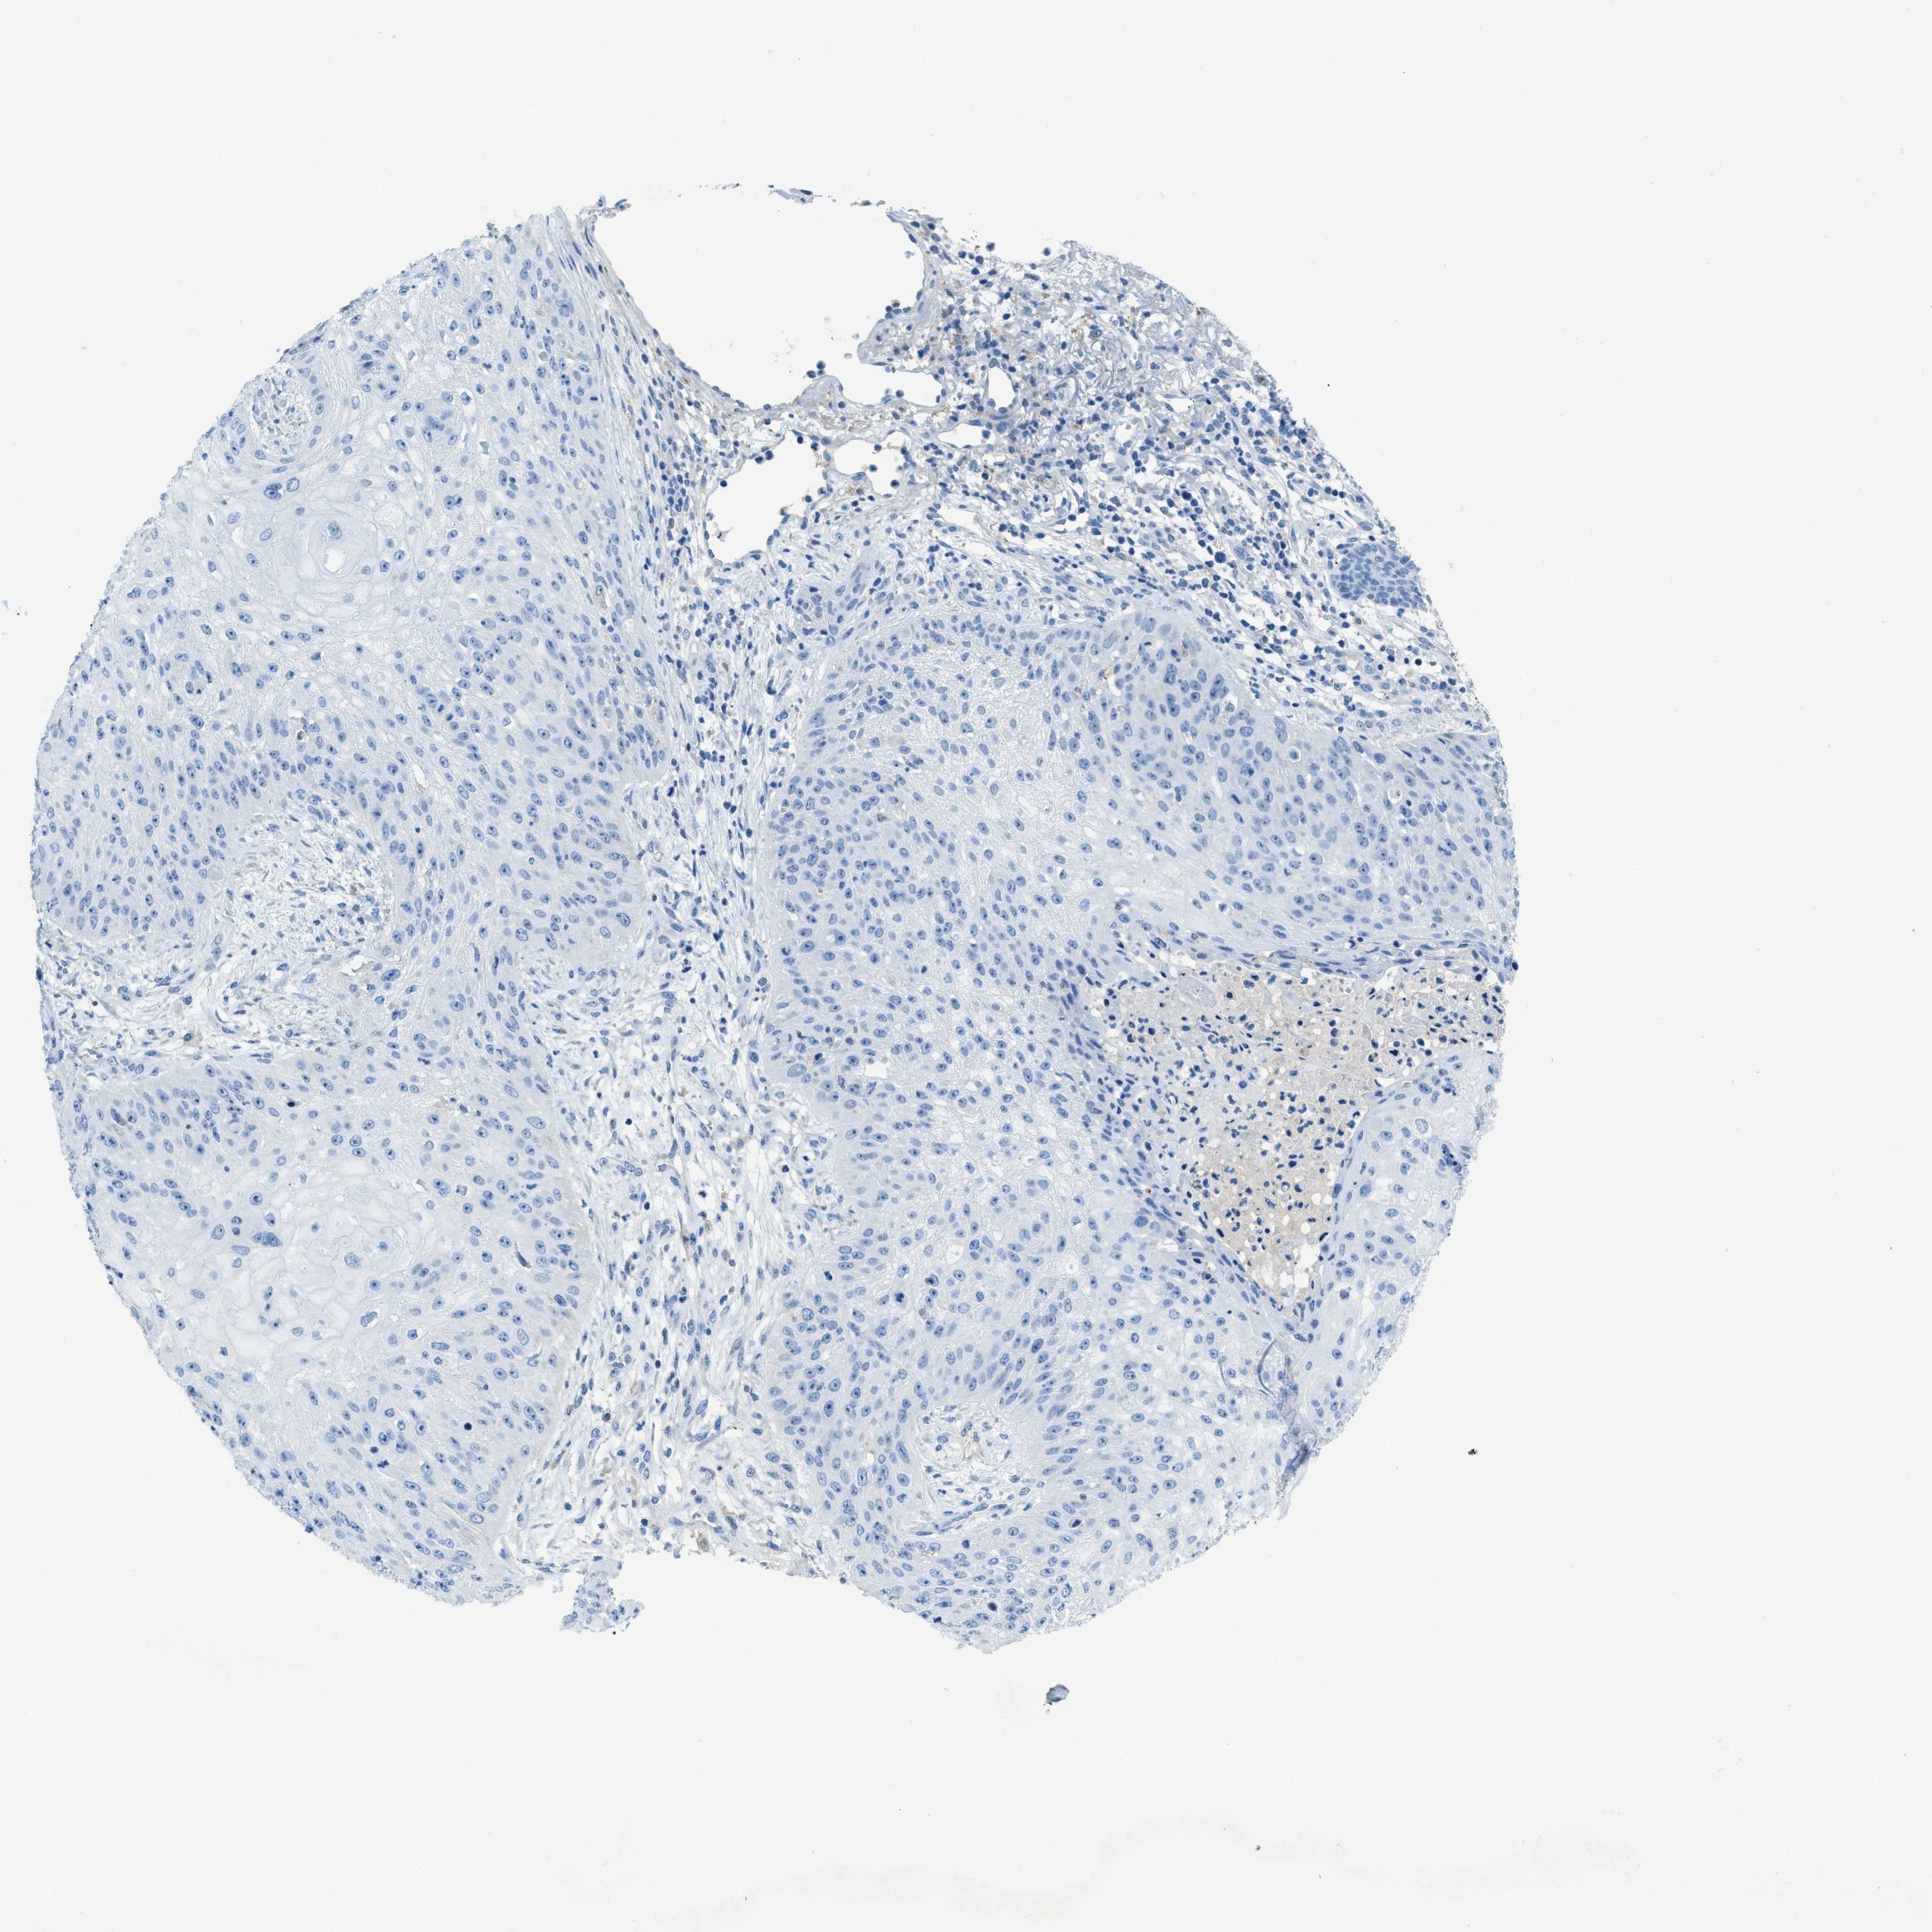

SKIN CANCER - Protein expressioni

A mouse-over function shows sample information and annotation data. Click on an image to view it in a full screen mode. Samples can be filtered based on level of antibody staining by selecting one or several of the following categories: high, medium, low and not detected. The assay and annotation is described here.

Each image is clickable and will lead to virtual microscopy that enables deeper exploration of all samples and also displays staining intensity scores, fraction scores and subcellular localization as well as patient and tissue information for each sample.

Antibody HPA017762

Squamous cell carcinoma, metastatic, NOS